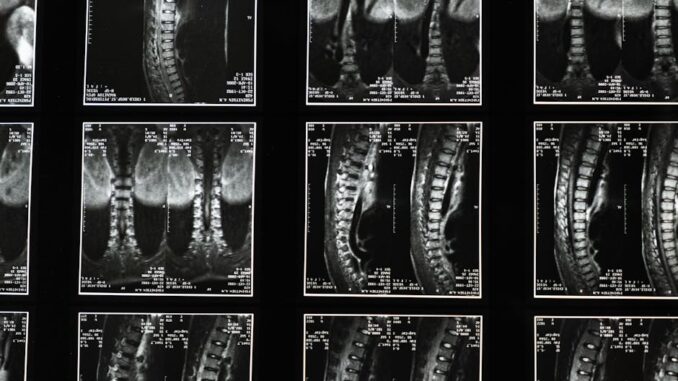

The goal? To develop and roll out AI tools that’ll speed up diagnosing and managing diseases like heart disease and cancer. Think about it: quicker diagnoses mean faster treatment, which, in turn, leads to better outcomes for patients. We’re talking about a real transformation in how healthcare operates. It’s about taking AI’s ability to crunch massive datasets and spot patterns that humans might miss, leading to earlier and more accurate diagnoses. Sounds promising, right? I remember a conversation I had with a colleague last year about the potential of AI in radiology, and this partnership seems like a solid step in that direction. And I can’t overstate the benefits, what is not to like?

They’re also diving into joint research projects, exploring new imaging methods and advanced scanning technologies. This dedication to research and development is crucial for keeping things moving forward in AI-driven diagnostics. They’re not just resting on their laurels; they’re actively looking for new and better ways to detect and manage diseases. It’s this kind of forward-thinking approach that will keep them at the forefront of medical technology.